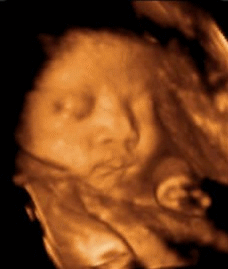

4.四维彩照只能看宝宝一举一动?

许多孕妈妈都很期待做四维彩超,因为这是准妈妈和胎宝的“第一次”见面,能够看到TA在肚子里或活泼或文静的可爱模样!但四维彩超更重要的作用是能够监测到胎宝宝的健康情况,进行排畸检查。

▶查看胎宝宝的活动

可以检查到胎宝宝在宫内是否缺氧,肢体运动、胎儿的吞咽动作等,能够很好地看到胎儿在孕妈妈体内的活动状况,说不定还可能看见宝宝做鬼脸、伸舌头哦。